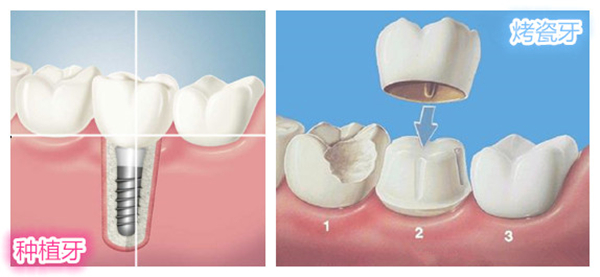

烤瓷牙修复牙齿好不好?安全吗?与种植牙如何选择?烤瓷牙与种植牙,都是修复牙齿的热门方式。廊坊圣洁口腔医院的医生指出:烤瓷牙胜在惰性合金金属、全瓷材料做基底,能提供良好的生物相容性,价格亲民;种植牙则拥有媲美真牙的咀嚼能力,是当今修复缺牙较棒的选择。如何选择取决你的实际需求。

1、牙齿局部缺损、牙根稳固,优先考虑烤瓷牙。

当龋齿、牙冠意外断折,牙根稳固的情况下,优先选择烤瓷牙,烤瓷牙价格实惠,专业修复后拥有真牙牙冠的通透性。 》》》相关阅读:廊坊市民烤瓷牙的寿命一般是多久

在费用上,烤瓷牙与普通的嵌体、树脂材料相差不大,但使用年限却更久,密合度高一样能保护原牙,这要看选择的医院与医生的技术水平。

首先,烤瓷牙按个数收费,通常掉牙1颗,需做3颗烤瓷牙,此时烤瓷牙费用与种植牙差别并不大了。 》》》相关阅读:廊坊哪些市民不适合做烤瓷牙?

其次,烤瓷牙修复缺牙后,仅能恢复30%的咀嚼能力,而种植牙能恢复95%。这意味着,烤瓷牙实用性欠佳,比如稍微硬一点的排骨、粘性大一些的粽子等烤瓷牙是不容易咀嚼的。

再次,种植牙的受力原理与真牙一致,种植牙能减缓牙槽骨萎缩,保护邻牙的稳定性。而烤瓷牙桥在受力时,会把力度向两边分散,造成邻牙受力过渡,进而崩瓷,损坏邻牙。

烤瓷牙修复缺牙,短期内看似有效,长远看损害了邻牙的健康,以后再想做种植,很大程度面临牙槽骨骨量不足、萎缩等问题,此时种牙难、费用高。